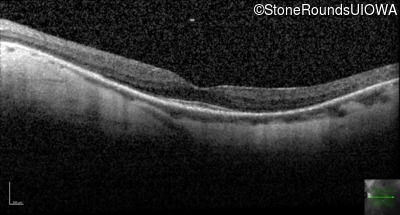

Optical Coherence Tomography - Left - 20/25 -1

Exemplar / OCT Stack

OCT Stack